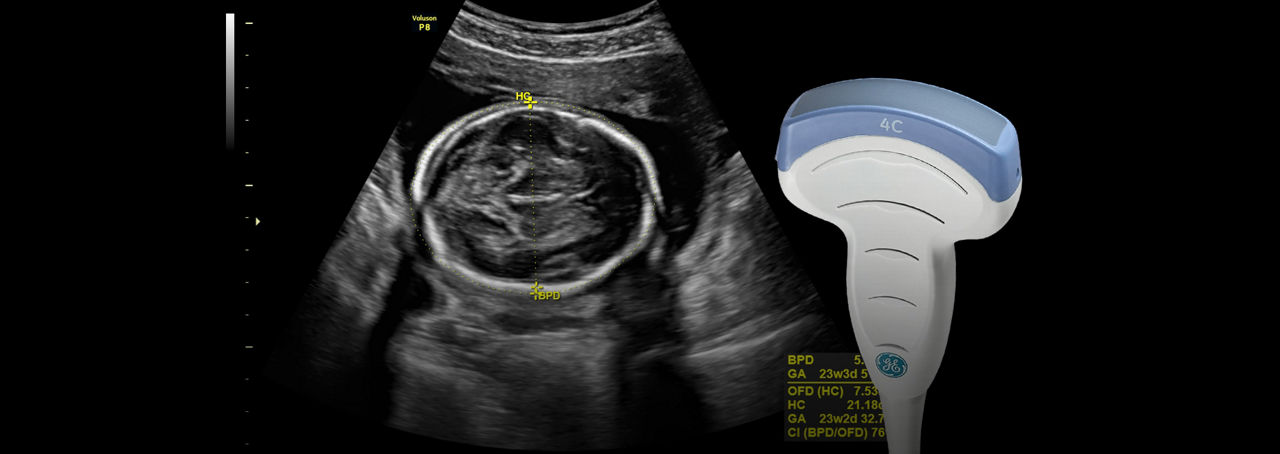

SonoBiometry

Reduce keystrokes with SonoBiometry – Semi-automated biometry measurements (BPD, HC, AC, FL, HL, Vp, CM, Cereb, FHR).

Uterine Classification

Simplify identification and reporting of uterine abnormalities based on ESHRE, ESGE, and ASRM guidelines.